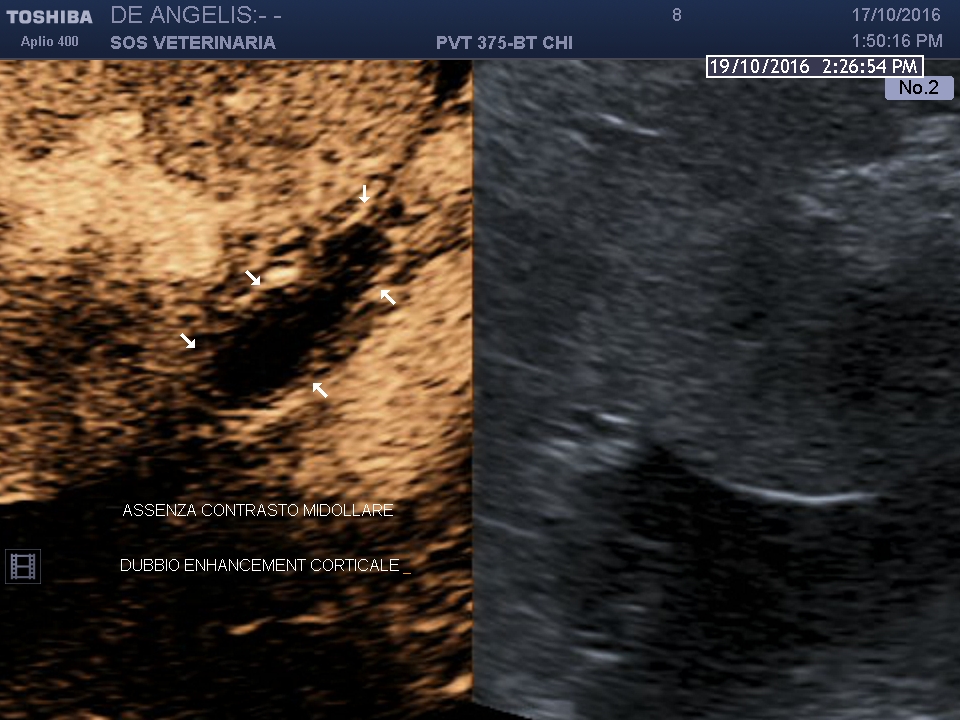

esame ecografico ceus

evidente assenza di enhancementin tutte le fasi forse un debole presa di contrasto sottocapsulare in periferia